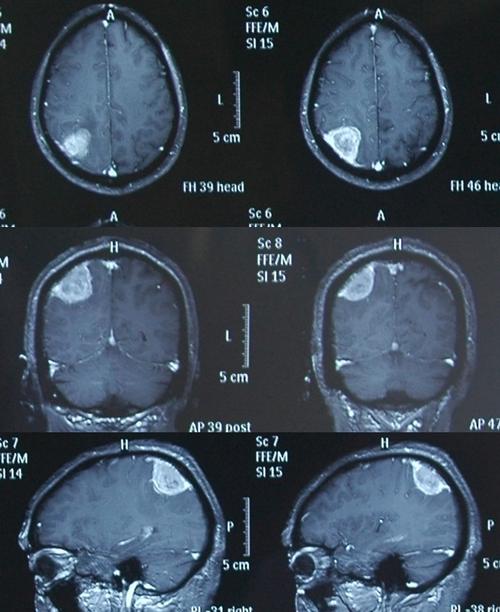

良性脑瘤的诊断

脑膜瘤多属良性,呈球形或结节

良性脑瘤图片

脑瘤图片

脑瘤片子照片

脑瘤图片大全真实